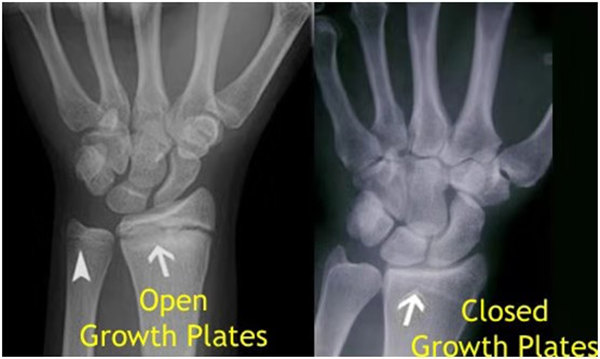

其實(shí)想要了解孩子的生長(zhǎng)發(fā)育情況或者說(shuō)孩子未來(lái)身高的趨勢(shì),測(cè)骨齡是個(gè)好辦法。臨床上通常拍攝兒童的左手正位X光片 , 采用《中華-05》骨齡標(biāo)準(zhǔn)對(duì)手腕骨發(fā)育程度進(jìn)行骨齡評(píng)價(jià)。

我們都知道,人體的高矮是由骨骼的生長(zhǎng)發(fā)育決定的,特別是下肢長(zhǎng)骨。長(zhǎng)骨呈長(zhǎng)管狀,在長(zhǎng)骨的兩端有一種專管骨骼生長(zhǎng)的骺軟骨,它與干骺端之間有一盤狀軟骨結(jié)構(gòu)稱為骺板(線),在幼兒的X光片上表現(xiàn)為一條較寬的透光帶。 (見下圖)

未成年時(shí)隨著年齡的增加骺軟骨端不斷骨化,骨骼就不斷增長(zhǎng)。當(dāng)骨骺線完全閉合時(shí)骨骼就停止生長(zhǎng),個(gè)子也就不再增長(zhǎng)了。一般骨骺端完全閉合的年齡是18~20歲左右。